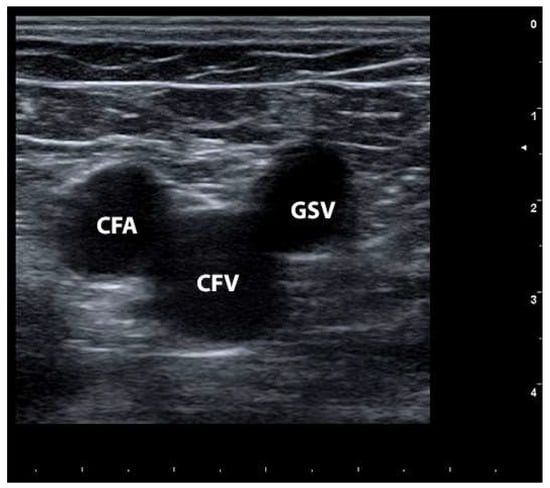

1.4. How Is It Possible to Diagnose CVD?